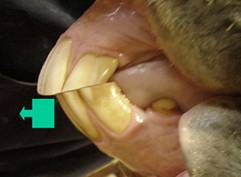

De mond van een paard wordt door paardentandarts Daan Staller zo behandeld dat er maximale bewegingsvrijheid van de onderkaak ten opzichte van de bovenkaak is. Hierdoor wordt tevens de mond in balans gebracht en neemt het druk van kaakgewricht en tanden en kiezen weg. Alle elementen worden ontdaan van scherpe randen en haken, dit doet paardentandarts Daan Staller zodanig grondig dat haken ed. lang wegblijven.

Door de eerste kiezen iets af te ronden creëert de paardentandarts bitseats. Door deze bitseats ligt het bit wat hoger en stabieler in de mond. Tandvlees, kaakbeen en tong komen vrijer te liggen, waardoor het bit niet hinderlijk in de mond licht, maar juist prettiger. De ruiter zal merken dat een paard makkelijker te rijden is.

Doordat een paard niet of nauwelijks graast, slijten de voortanden te weinig. Dit tekort aan slijtage geeft problemen welke worden verholpen en voorkomen door ze tot de juiste lengte in te korten.

Het paard heeft na behandeling een meer gelijkmatig slijtage-druk verhouding op de kiezen, waardoor de levensduur van de tanden en het paard langer is.